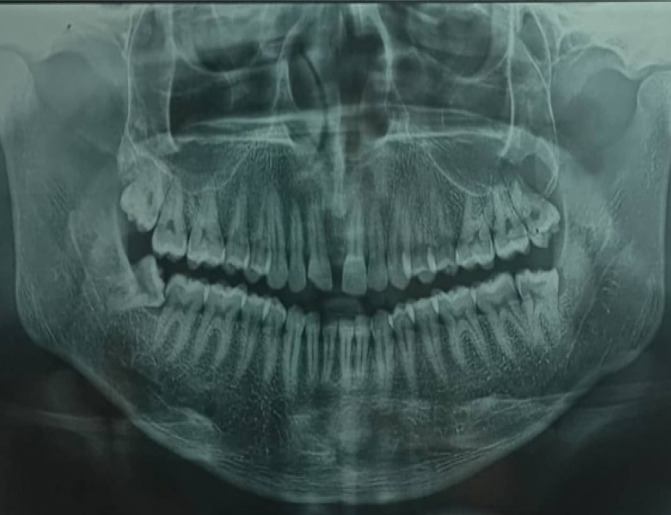

Odontogenic keratocyst is a benign intraosseous lesion of odontogenic origin which is characterized by its aggressive nature. It is usually present in the mandibular posterior area, although it can also be found in the maxilla, particularly in the canine region. We discuss a unique example of OKC in the maxillary sinus involving the 27&28 region. Due to comparable clinical signs, this lesion is more prone to be mistaken for other lesions of the maxillary sinus, such as sinusitis or polyps. On the other side, this benign disease has the potential to develop into Ameloblastoma or squamous cell carcinoma. A favorable prognosis thus depends on early identification, precise diagnosis, appropriate treatment, and follow-ups.